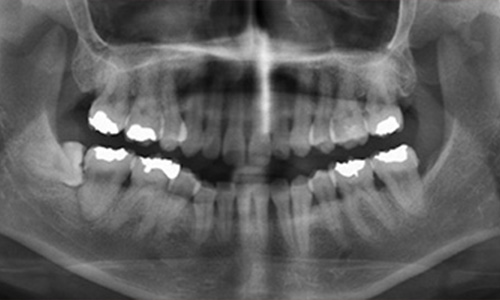

レントゲン写真の歯槽骨の頂点に線を引いていますが、線は波をうったような状態になっています。写真の口腔内では炎症は部分的に認められます。そして全体的に歯肉が下がり、「すきま」ができています。歯根が少し見えてくるため、歯が長くなったような状態になっています。